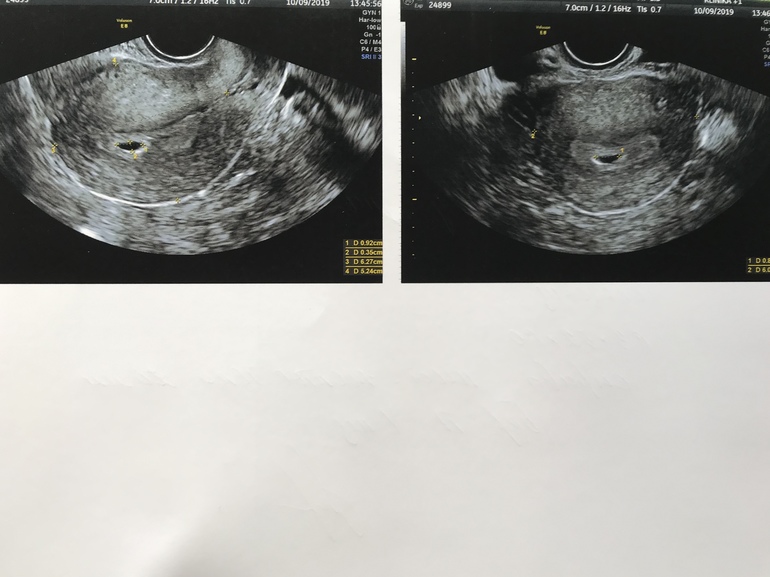

Узи 5 недель и 5 дней

По узи срок 4 эмбриональных недели , поэтому увидели только плодное яйцо и жт

Через неделю повторное

Собственно мне самое главное было узнать что бусинка моя в матке прикрепилась , и что нет отслоек , гематом и т.д.